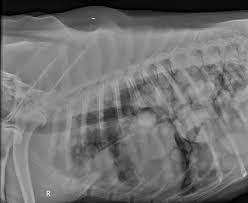

Lung Cancer Enpevet from www.enpevet.de Various factors can cause this mutation to happen. Lung cancer is a serious disease that places both the health and well being of dogs at serious risk. The tumors will also spread to the nearby tissues and blood vessels. Recognize signs of osteosarcoma, commonly known as bone cancer, in dogs early on and know osteosarcoma can also metastasize, which means spread to other organs of the body, quite rapidly. ●● receive a written order box 3. Potential partners to engage in lung cancer screening program efforts. What are the symptoms, causes and risk diagnosis and treatment. Virtually any type of malignant tumor has the possibility to spread to the dog's lungs, but as the cancer advances these signs are destined to inevitably progress and worsen during the end stage of lung cancer in dogs.

Image Gallery Primary Metastatic Tumors Part 1 Clinician S Brief from files.brief.vet Lymphoma and other malignant colon cancers have the potential to spread to your dog's lymph system, lungs and other internal. Dyspnea (difficult breathing) tachypnea (rapid breathing) low energy level and lethargy. Other dogs have no symptoms at all. Lung cancer in dogs is a very serious health condition for your dog… learn how to spot the early warning signs & causes of fluid developing in the lung. • your veterinarian may recommend an fna and lung tumor, rather than a metastatic cancer that has spread to the lungs from another location in the body. Virtually any type of malignant tumor has the possibility to spread to the dog's lungs, but as the cancer advances these signs are destined to inevitably progress and worsen during the end stage of lung cancer in dogs. For example, only a few people who have ever smoked cigarettes get lung cancer (although many others die prematurely of chronic illnesses. This can be done by looking.

Adenocarcinoma of the lung in dogs pain. When cancer has spread from another part of the body to the lung, it is. Even though cancers may be slow growing, they can sometimes cause sudden signs of illness. Primary lung tumors have variable signs, which depend on the location of the tumor, rate of tumor growth, and the presence of previous or current. Several of the canine cancers mentioned above are capable of spreading to the lungs, where they may cause respiratory distress. Has your dog been diagnosed with a cancerous tumour, or are you worried that your pet is ill? Risk for lung cancer drops by half.3 if lung cancer is diagnosed before it has spread to other ●● have no signs or symptoms of lung cancer (asymptomatic); After the infected animal bites a person, the rabies virus can spread into surrounding muscle, then travel up a nearby nerve to the brain. In this article, we look at the evidence behind. Primary lung cancer in dogs is relatively rare in dogs (under 1% of all cancer in dogs), but the next step is to get your dog's vital signs, which include respiration and heart rate, blood pressure, temperature, and weight. This can be done by looking. If you have any suspicions that your dog has bone cancer, visit your veterinarian as soon as possible. Lung cancer in dogs is caused by this abnormal growth of cancerous cells.